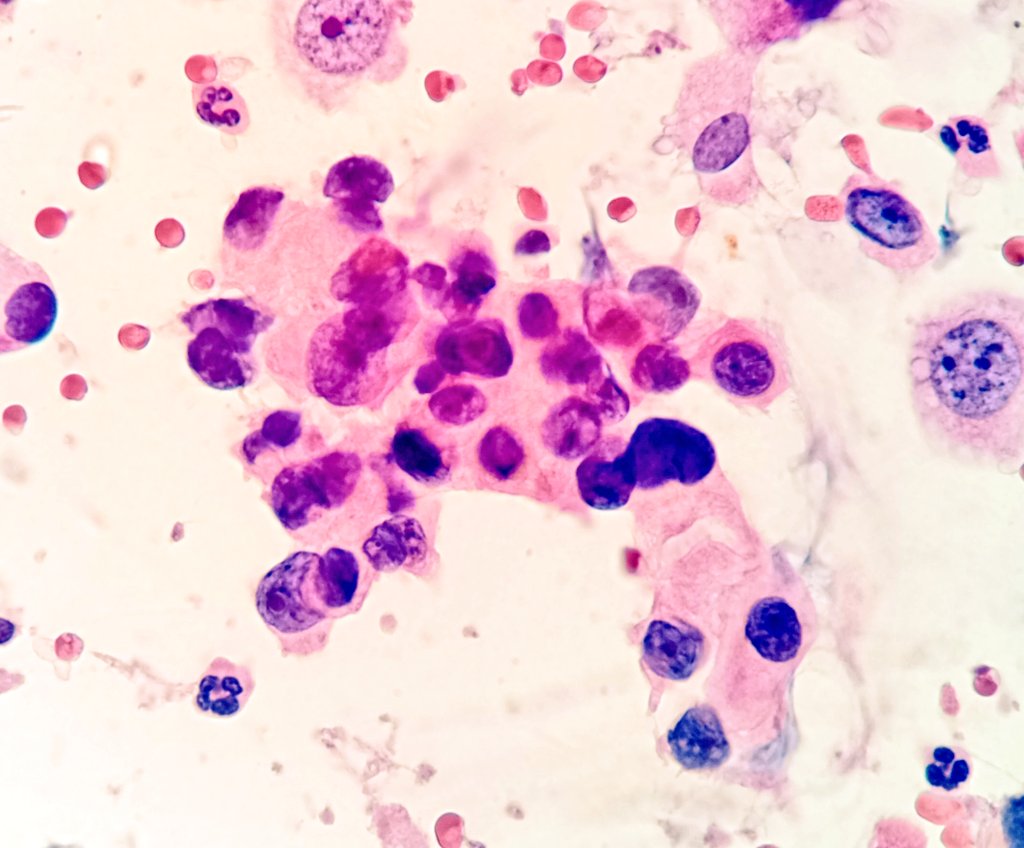

The frozen section